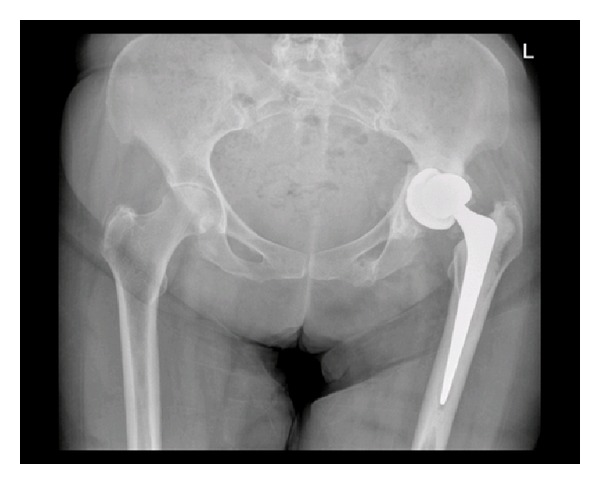

A 64-year-old lady with past medical history of learning difficulties and osteoarthritis presented to our emergency department following a mechanical trip and fall landing onto her left side. Detailed history and examination revealed pain and tenderness in the left groin over the inferior pubic ramus. The patient had pain on weight-bearing on the left side. She had previously undergone a left THR seven months earlier (Figure 1) and had been ambulating well without any problems since. Plain pelvic radiographs taken on this admission revealed only an isolated minimally displaced fracture of the left inferior pubic ramus (Figure 2). The patient was treated with analgesia and early mobilisation within the range of comfort with crutches. No followup was arranged and the patient was not discussed with the orthopaedic team.

Figure 1.

Plain radiograph taken on day 1 after initial left total hip arthroplasty.